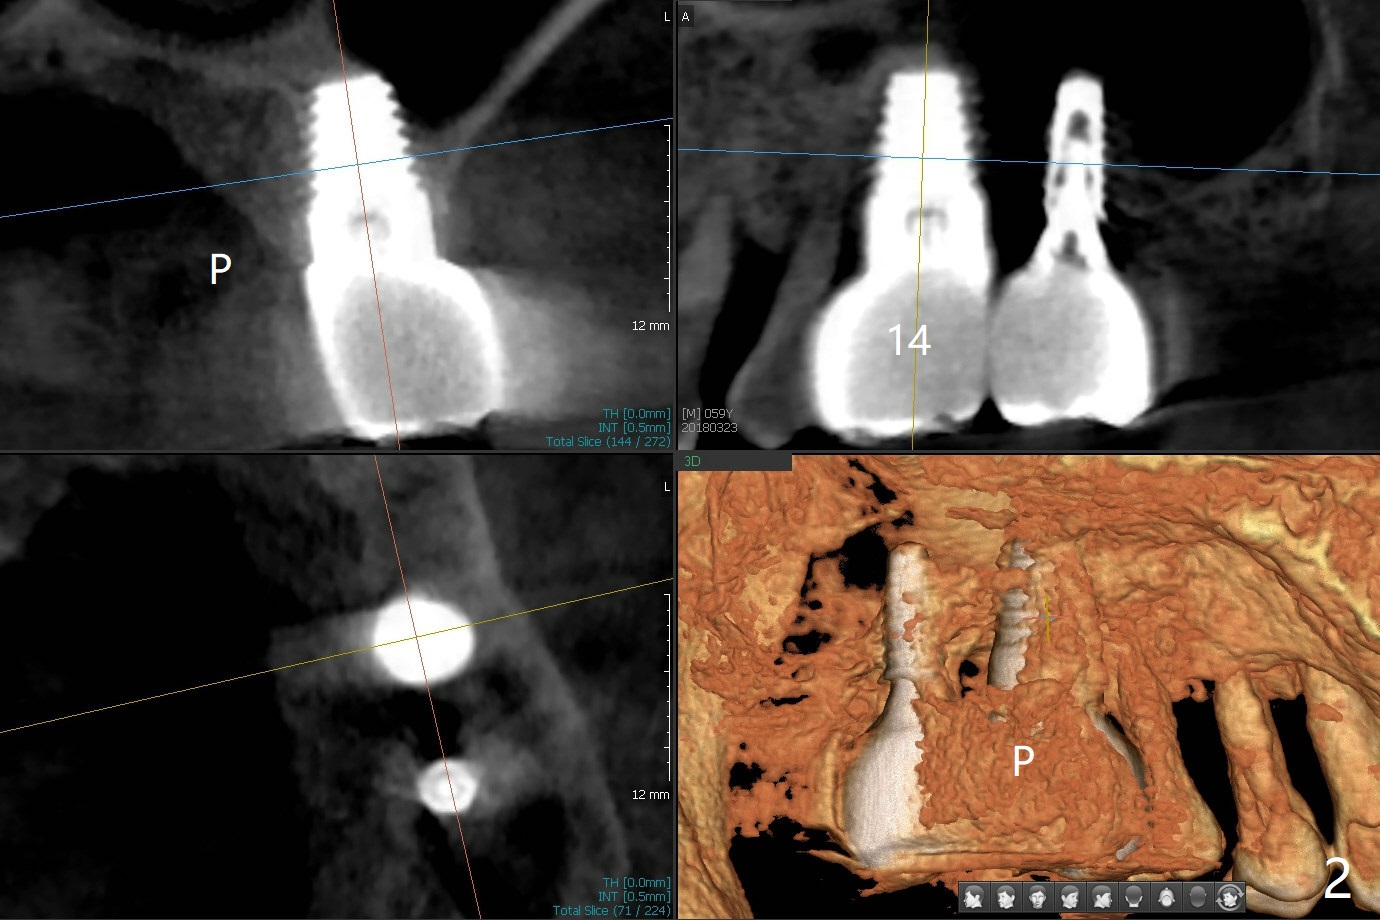

Remove 8x14 mm Implant

A 61-year-old man has gingival hemorrhage from #14. There are deep palatal pockets with bleeding on probing (Fig.1). The large tissue-level implant was placed to replace a loose 6x11 mm one 7 years ago. CT taken <2 years ago shows no palatal bone (Fig.2; periimplantitis). Prepare 8/9 mm trephine bur, although it is most likely not appropriate because of its inherent abutment. Draw 3 tubes of blood for PRF and sticky bone for bone graft. The tooth #13 may need DO composite (Fig.1 *) or extraction. The crown/abutment of #15 may be removed for easy access to #14. The abutment at #14 is 6 mm 10 degree, cemented with Ketac. Prepare high speed handpiece to section the crown and make slot on the abutment and heat autoclave Husky Microdriver.